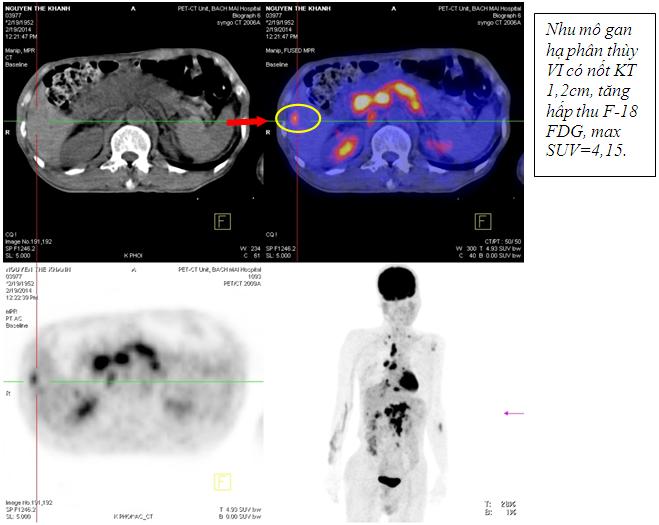

Kết quả chụp PET/CT: Khối vùng phế quản gốc phải KT 2,4x1,7cm; maxSUV=8,50; Hạch dưới carina KT 3,1x3,5cm ; maxSUV=8,50;Nhiều hạch ổ bụng dọc theo ĐMchủ bụng tạo thành khối lớn KT 8,5x5,1cm và 5,1x3,9cm, tăng hấp thu F-18 FDG, maxSUV=10,45; Hạch thượng đòn phải KT 1,1cm, tăng hấp thu F-18 FDG, max SUV=5,67; Hạch thượng đòn trái KT 0,8cm, max SUV=3,97; Tổn thương cung sau xương sườn số 2 bên phải tăng hấp thu F-18 FDG, max SUV=3,13; Nhu mô gan hạ phân thùy VI có nốt KT 1,2cm, tăng hấp thu F-18 FDG, max SUV=4,15.